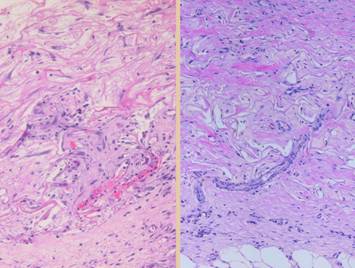

Normal post-inflammatory wound healing and its resulting scar are very different than Integra histogenesis with its normal dermal qualities.  Despite the nominal similarity of the two – a collection of angiocytes and fibroblasts and the vessels and connectives they make – they are each organized in patterns and structural mechanics that are fundamentally different from each other.  These differences can be appreciated grossly and clinically and also histologically.

Left upper, Integra on a thigh.  The matrix as seen through the silicone is regenerated properly into a neodermis.  In a seam between two pieces of Integra, a small open gap has resulted in normal wound healing, recognized by the bead of granulation tissue that has arisen.  Left lower, a similar situation in another patient.  The Integra reconstructed skin is flat and soft and of normal color.  In the center is a hypertrophic scar where the gap between Integra edges allowed normal wound healing.  Center upper, an old trauma scar across the ankle.  Scar is resisting movement and becoming more tendinous and stiff, causing the scar to fracture and ulcerate from normal ankle motion which in turn perpetuates the scar, inflammation, and ulcer.  Center lower, Integra reconstructed skin on the dorsum of the hand following trauma.  Just a few weeks after skin graft placement, the neodermis is soft, compliant, and pliable to a degree comparable to normal skin.  Right, a microscopic view of regenerating Integra.  The dissimilarities of scar and Integra were seen on the last panel.  This view shows a syncytial cluster, a histologic structure that is seen in embryonic dermatogenesis and in Integra regeneration, but never in normal post-inflammatory wound healing.  This structure, explained on subsequent panels, is the basis for Integra’s biological, mechanical, and clinical properties

Left, a microscope image of normal wound healing.  The structure shown here is the prototypical wound.  Details of the structure and process will be explained in following panels.  Right, the microscopic appearance of fully regenerated Integra-CG matrix, the details likewise to be explained in following panels.  Even without explaining or focusing on specific details, the dissimilarity of the two can be appreciated.  Angiocytes and fibroblasts, vessels and connectives – that is all there is to these two tissues.  However, by supplying different “rules” or “subroutines” for the interaction and assembly of these elements, two different biomaterials emerge.  The rules or routines are based on the circumstances, reaction-to-injury versus embryonic regeneration.  The results have very different physical properties and implications for daily life, functional adaptations, and potential need for ongoing medical care.